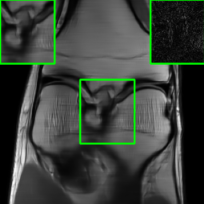

In Fig. 1-(a) and (b), we show reconstructed images using MoDL originating from a benign (i.e., undisturbed) input and a PGD scheme-perturbed input, respectively. It is evident that the worst-case input disturbance significantly deteriorates the quality of the reconstructed image. While one focus of this work is to enhance robustness against input perturbations, Fig.1-(c) and (d) highlight two additional potential sources of instability that the reconstructor (MoDL) can encounter during testing: variations in the measurement sampling rate (resulting in “perturbations” to the sparsity of the sampling mask in ) [20] and changes in the number of unrolling steps [22]. In scenarios where the sampling mask (Fig.1-(c)) or number of unrolling steps (Fig.1-(d)) deviate from the settings used during MoDL training, we observe a significant degradation in performance compared to the original setup (Fig.1-(a)), even in the absence of additive measurement perturbations. In Section IV, we demonstrate how our method improves the reconstruction robustness in the presence of different types of perturbations, including those in Fig.1.

Table II compares image reconstruction quality with different methods at two sampling acceleration factors for the knee dataset. We observe quite similar and congruous outcomes to those reported in Table I. Figs. 6 and 7 show reconstructed images by different methods for knee scans at 4x and 8x undersampling, respectively. We observe that SMUG and Weighted SMUG show fewer artifacts, sharper features, and fewer errors when compared to Vanilla MoDL reconstruction in the presence of the worst-case perturbations.